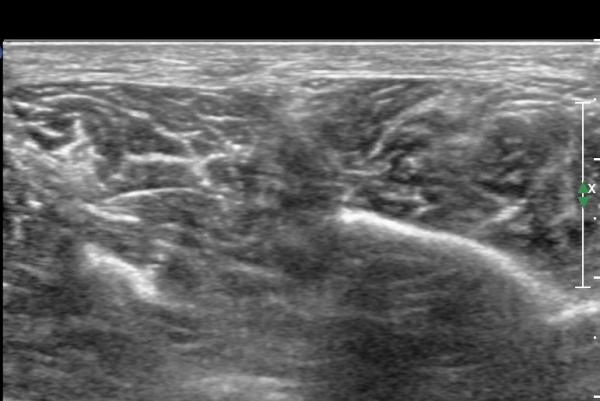

¾Æ·§´Ù¸® ¿ÜÃø Ⱦ´Ü¸é°Ë»ç¿¡¼ Àåºñ°ñ±Ù°ú ¹ß°¡¶ô½ÅÀü±Ù »çÀÌ¿¡¼ õºñ°ñ½Å°æÀÌ Á¤»óÀûÀ¸·Î °üÂûµÈ´Ù(»çÁø 1, , 2, 3, 4, 5).